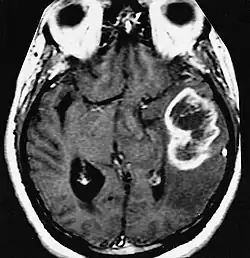

| MRI showing a ring-enhancing lesion in the brain of a patient with glioblastoma multiforme | |

A ring-enhancing lesion is an abnormal radiologic sign on MRI or CT scans obtained using radiocontrast. On the image, there is an area of decreased density (see radiodensity) surrounded by a bright rim from concentration of the enhancing contrast dye. This enhancement may represent breakdown of the blood-brain barrier and the development of an inflammatory capsule. This can be a finding in numerous disease states. In the brain, it can occur with an early brain abscess as well as in Nocardia infections associated with lung cavitary lesions. In patients with HIV, the major differential is between CNS lymphoma and CNS toxoplasmosis. CT imaging is the appropriate next step to differentiate between the two conditions.[1]